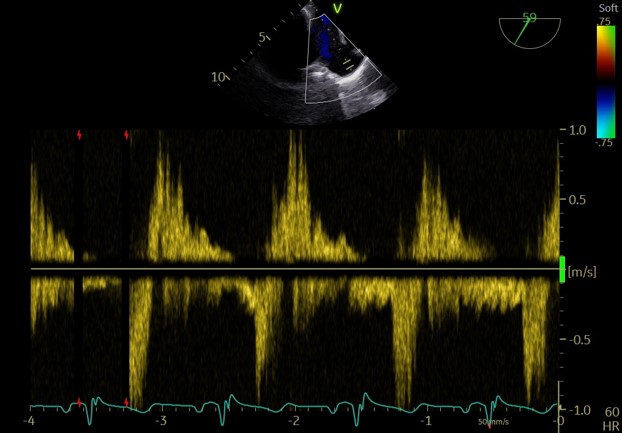

释放后

外侧2偏1区可见后叶栓系,下方空间乳头肌腱索杂多,后叶长度也一般,跨瓣压差3mmHg,第三枚夹子选择了NT,打算靠近第一枚夹子2偏1区夹持,置入NT后,在1区上方做轨迹测试,充分释放张力,调整夹子的夹臂方向位于1点-7点的方向,回拉系统,使第三枚夹子靠近第一枚夹子,关小夹子进入到心室侧,由于第一枚夹子起到了稳定瓣叶的作用,第三枚夹子捕捞夹持相对顺利,一次精准捕获前叶和后叶,再次完整评估二尖瓣NT的方向、组织桥稳定性、瓣叶受限程度及反流减小程度。反流改善到1+-2+,平均跨瓣压差3.85mmHg,左房压明显下降,肺静脉逆流明显改善,手术完美结束。

术后平均跨瓣压差

术后左房压